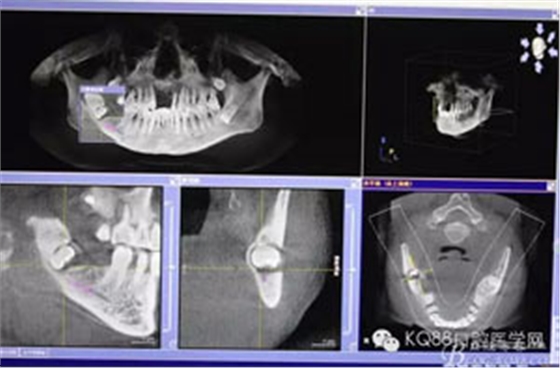

圖3.其他方向的影像檢查:48近中牙冠與下頜管之間無骨壁相隔。

圖4.總體的CBCT影像: